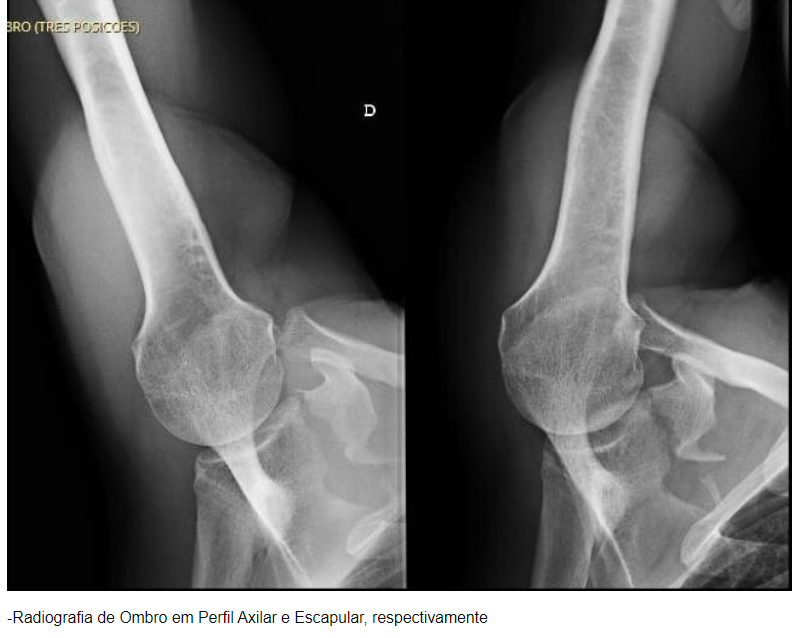

Quais incidências radiográficas são indicadas para fratura do úmero proximal?

A

AP, perfil da escápula e axilar.

Axilar é ótima para avaliar a relação entre a cabeça umeral e a glenóide, mas pode ser desconfortável.

Escapular (Y) é ideal para diagnosticar luxações posteriores e fraturas da escápula, com uma visão clara da anatomia escapular.